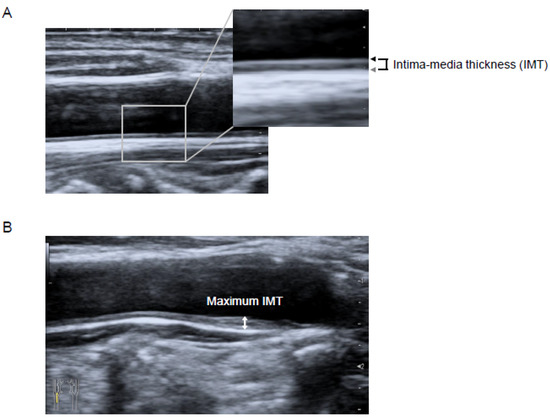

2.5. Ultrasonographic Measurement of Carotid IMT

| Maximum IMT of carotid artery (mm) | 2.5 ± 0.7 |

- Hirano, M.; Nakamura, T.; Kitta, Y.; Takishima, I.; Deyama, J.; Kobayashi, T.; Fujioka, D.; Saito, Y.; Watanabe, K.; Watanabe, Y.; et al. Short-term progression of maximum intima-media thickness of carotid plaque is associated with future coronary events in patients with coronary artery disease. Atherosclerosis 2011, 215, 507–512. [Google Scholar] [CrossRef] [PubMed]